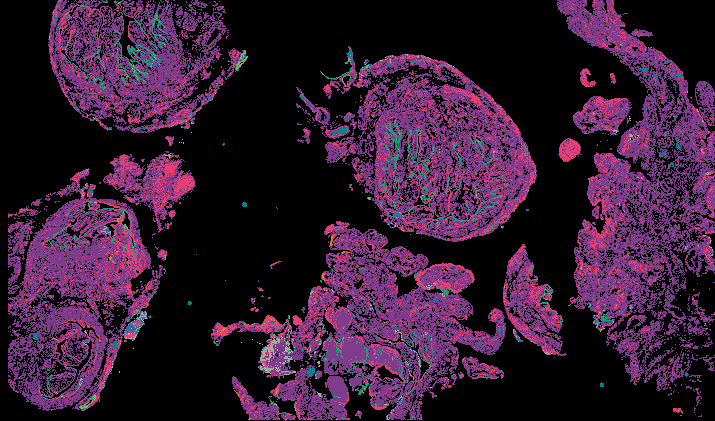

Curated stories provide access to images that have undergone a quality control step to remove failed markers, ensure appropriate channel intensity settings, and provide metadata about the underlying sample and image. Click the Minerva story icon for an interactive view of the full-resolution images.

Data image

LSP11060

LSP11064